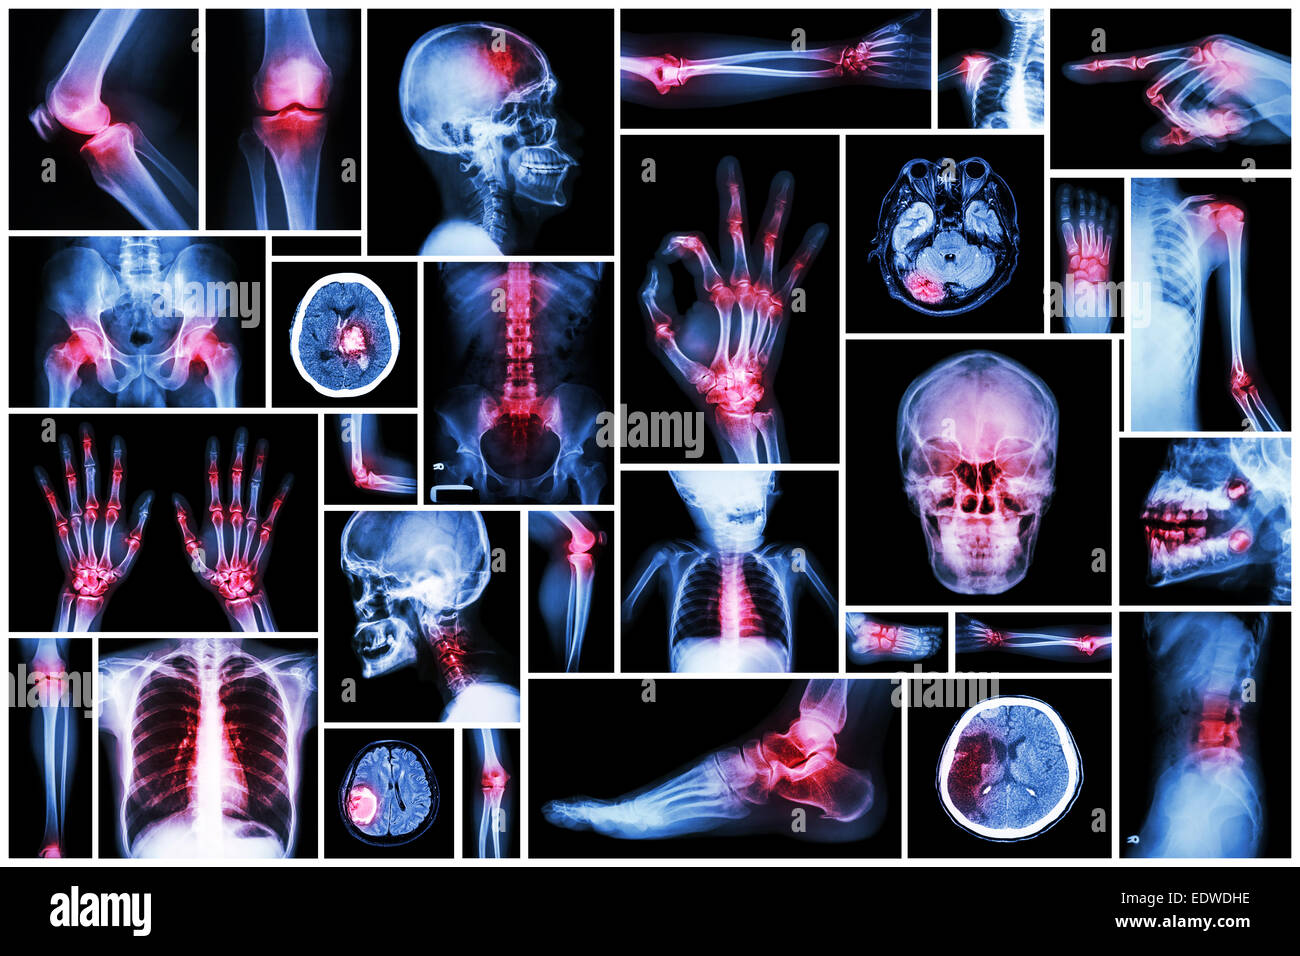

Collection X-ray et d'organes multiples à l'arthrite rhumatoïde (commune de multiples,la goutte) Banque D'Imageshttps://www.alamyimages.fr/image-license-details/?v=1https://www.alamyimages.fr/photo-image-collection-x-ray-et-d-organes-multiples-a-l-arthrite-rhumatoide-commune-de-multiples-la-goutte-77392076.html

Collection X-ray et d'organes multiples à l'arthrite rhumatoïde (commune de multiples,la goutte) Banque D'Imageshttps://www.alamyimages.fr/image-license-details/?v=1https://www.alamyimages.fr/photo-image-collection-x-ray-et-d-organes-multiples-a-l-arthrite-rhumatoide-commune-de-multiples-la-goutte-77392076.htmlRFEDWEAM–Collection X-ray et d'organes multiples à l'arthrite rhumatoïde (commune de multiples,la goutte)

Collection X-ray et d'organes multiples à l'arthrite rhumatoïde (commune de multiples,la goutte) Banque D'Imageshttps://www.alamyimages.fr/image-license-details/?v=1https://www.alamyimages.fr/photo-image-collection-x-ray-et-d-organes-multiples-a-l-arthrite-rhumatoide-commune-de-multiples-la-goutte-77392073.html

Collection X-ray et d'organes multiples à l'arthrite rhumatoïde (commune de multiples,la goutte) Banque D'Imageshttps://www.alamyimages.fr/image-license-details/?v=1https://www.alamyimages.fr/photo-image-collection-x-ray-et-d-organes-multiples-a-l-arthrite-rhumatoide-commune-de-multiples-la-goutte-77392073.htmlRFEDWEAH–Collection X-ray et d'organes multiples à l'arthrite rhumatoïde (commune de multiples,la goutte)

Collection X-ray partie multiples des droits de l'arthrite et la goutte (maladie,plusieurs , la polyarthrite rhumatoïde, la maladie de coeur congénitale,course) Banque D'Imageshttps://www.alamyimages.fr/image-license-details/?v=1https://www.alamyimages.fr/photo-image-collection-x-ray-partie-multiples-des-droits-de-l-arthrite-et-la-goutte-maladie-plusieurs-la-polyarthrite-rhumatoide-la-maladie-de-coeur-congenitale-course-77404848.html

Collection X-ray partie multiples des droits de l'arthrite et la goutte (maladie,plusieurs , la polyarthrite rhumatoïde, la maladie de coeur congénitale,course) Banque D'Imageshttps://www.alamyimages.fr/image-license-details/?v=1https://www.alamyimages.fr/photo-image-collection-x-ray-partie-multiples-des-droits-de-l-arthrite-et-la-goutte-maladie-plusieurs-la-polyarthrite-rhumatoide-la-maladie-de-coeur-congenitale-course-77404848.htmlRFEDX2JT–Collection X-ray partie multiples des droits de l'arthrite et la goutte (maladie,plusieurs , la polyarthrite rhumatoïde, la maladie de coeur congénitale,course)

X-ray plusieurs partie de la avec de multiples maladies (accident vasculaire cérébral, l'arthrite, la goutte, le rhumatisme, tumeur au cerveau, l'arthrose, etc.) Banque D'Imageshttps://www.alamyimages.fr/image-license-details/?v=1https://www.alamyimages.fr/photo-image-x-ray-plusieurs-partie-de-la-avec-de-multiples-maladies-accident-vasculaire-cerebral-l-arthrite-la-goutte-le-rhumatisme-tumeur-au-cerveau-l-arthrose-etc-77391487.html

X-ray plusieurs partie de la avec de multiples maladies (accident vasculaire cérébral, l'arthrite, la goutte, le rhumatisme, tumeur au cerveau, l'arthrose, etc.) Banque D'Imageshttps://www.alamyimages.fr/image-license-details/?v=1https://www.alamyimages.fr/photo-image-x-ray-plusieurs-partie-de-la-avec-de-multiples-maladies-accident-vasculaire-cerebral-l-arthrite-la-goutte-le-rhumatisme-tumeur-au-cerveau-l-arthrose-etc-77391487.htmlRFEDWDHK–X-ray plusieurs partie de la avec de multiples maladies (accident vasculaire cérébral, l'arthrite, la goutte, le rhumatisme, tumeur au cerveau, l'arthrose, etc.)

X-ray plusieurs partie de la avec de multiples maladies (accident vasculaire cérébral, l'arthrite, la goutte, le rhumatisme, tumeur au cerveau, l'arthrose, etc.) Banque D'Imageshttps://www.alamyimages.fr/image-license-details/?v=1https://www.alamyimages.fr/photo-image-x-ray-plusieurs-partie-de-la-avec-de-multiples-maladies-accident-vasculaire-cerebral-l-arthrite-la-goutte-le-rhumatisme-tumeur-au-cerveau-l-arthrose-etc-77391482.html

X-ray plusieurs partie de la avec de multiples maladies (accident vasculaire cérébral, l'arthrite, la goutte, le rhumatisme, tumeur au cerveau, l'arthrose, etc.) Banque D'Imageshttps://www.alamyimages.fr/image-license-details/?v=1https://www.alamyimages.fr/photo-image-x-ray-plusieurs-partie-de-la-avec-de-multiples-maladies-accident-vasculaire-cerebral-l-arthrite-la-goutte-le-rhumatisme-tumeur-au-cerveau-l-arthrose-etc-77391482.htmlRFEDWDHE–X-ray plusieurs partie de la avec de multiples maladies (accident vasculaire cérébral, l'arthrite, la goutte, le rhumatisme, tumeur au cerveau, l'arthrose, etc.)